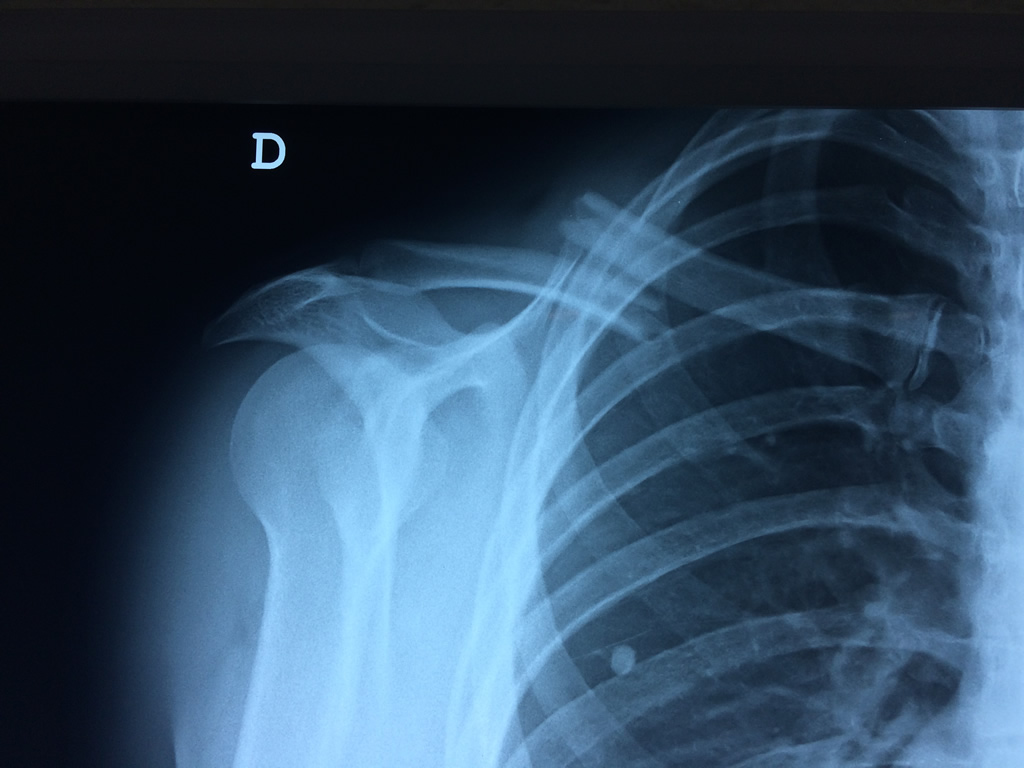

Cirugias en El Salvador - Clavícula